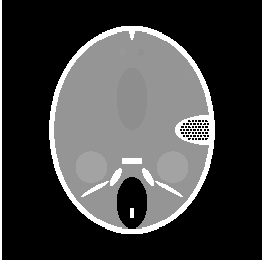

In this section we report the results of several tests run on simulated under-sampled data obtained by synthetic (phantoms) and full resolution MRI images. The under-sampled data are obtained as where is the full resolution image and is the under-sampling Fourier matrix, obtained as in (5). The under-sampling masks, analyzed in the next paragraphs are: radial mask (), parallel mask () and random mask (). In figure 1 we represent an example of each mask with low sampling rate , measured by the percentage ratio between the number of non-zero pixels and the total number of pixels :

| (48) |

In this paragraph we test the performance of FNCR algorithm in reconstructing good quality images from highly under-sampled data. We focus on two synthetic images: the Shepp-Logan phantom (T1) (figure 2(a)), widely used in algorithm testing, and the Forbild phantom (T2) [21] (figure 2(b)), well known as a very difficult test problem.

Concerning the real MRI data we compare IL and FNCR algorithms in the reconstructions of the brain image (T3 test), represented in figure 8. We report in table 6 the results obtained by reconstructing the noiseless data undersampled by , , masks.